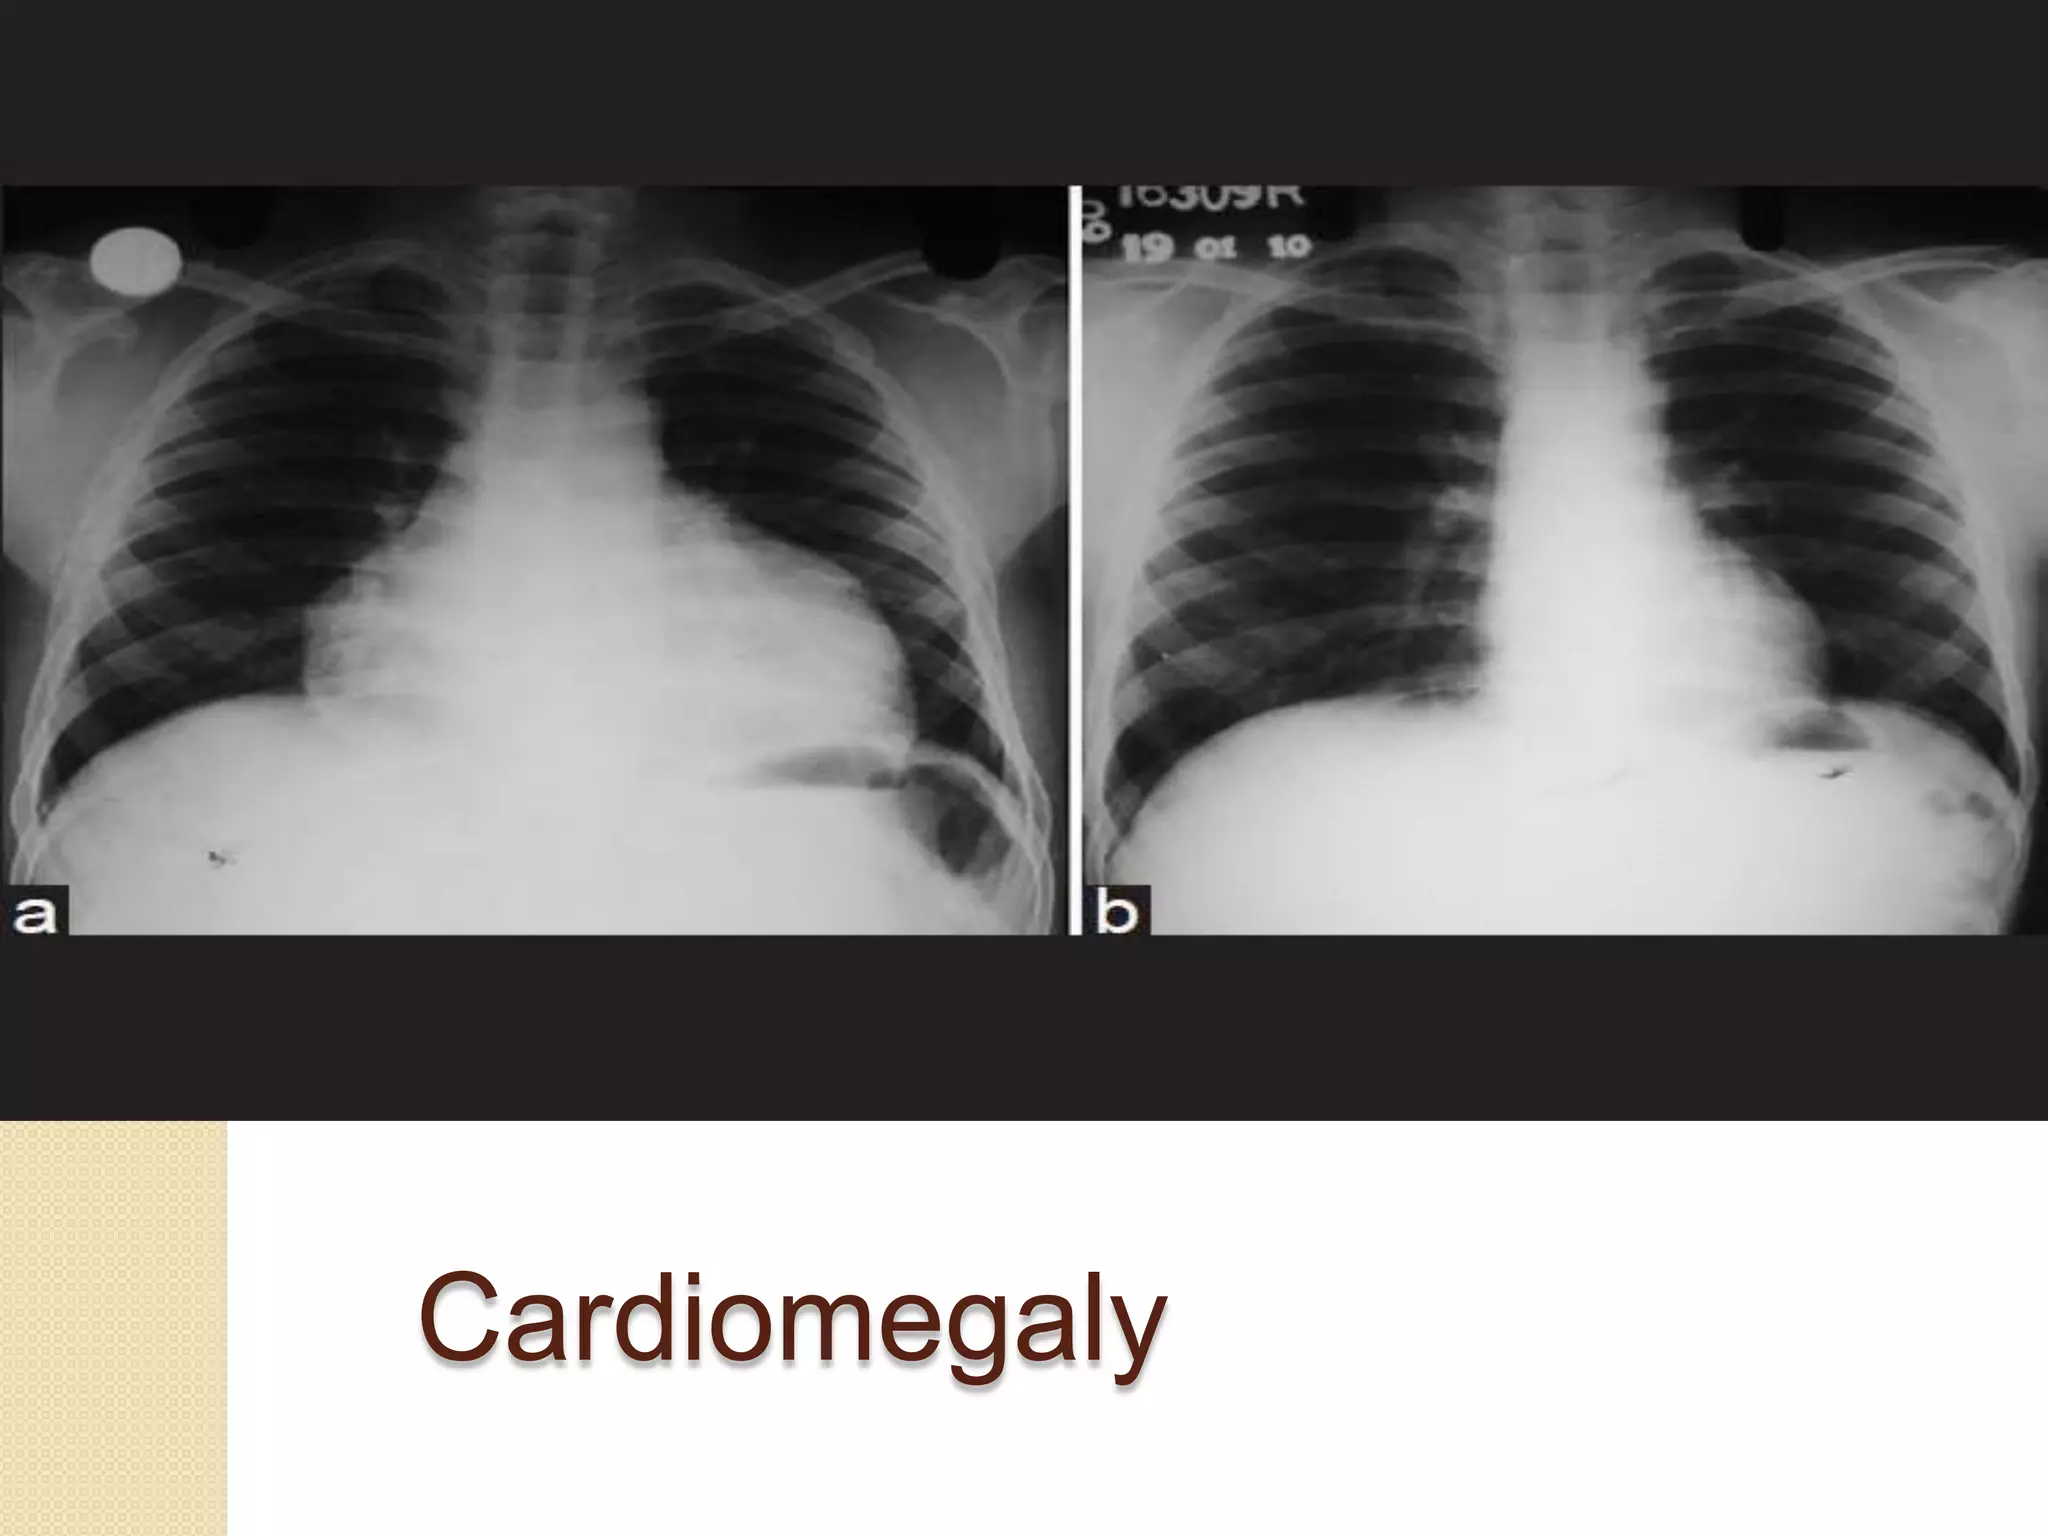

 The main advantages of the chest

X-ray are in differentiating primary

lung disease from heart disease

and in providing a clear view of

anatomical abnormalities such as

heart enlargement.

Cardiomegaly